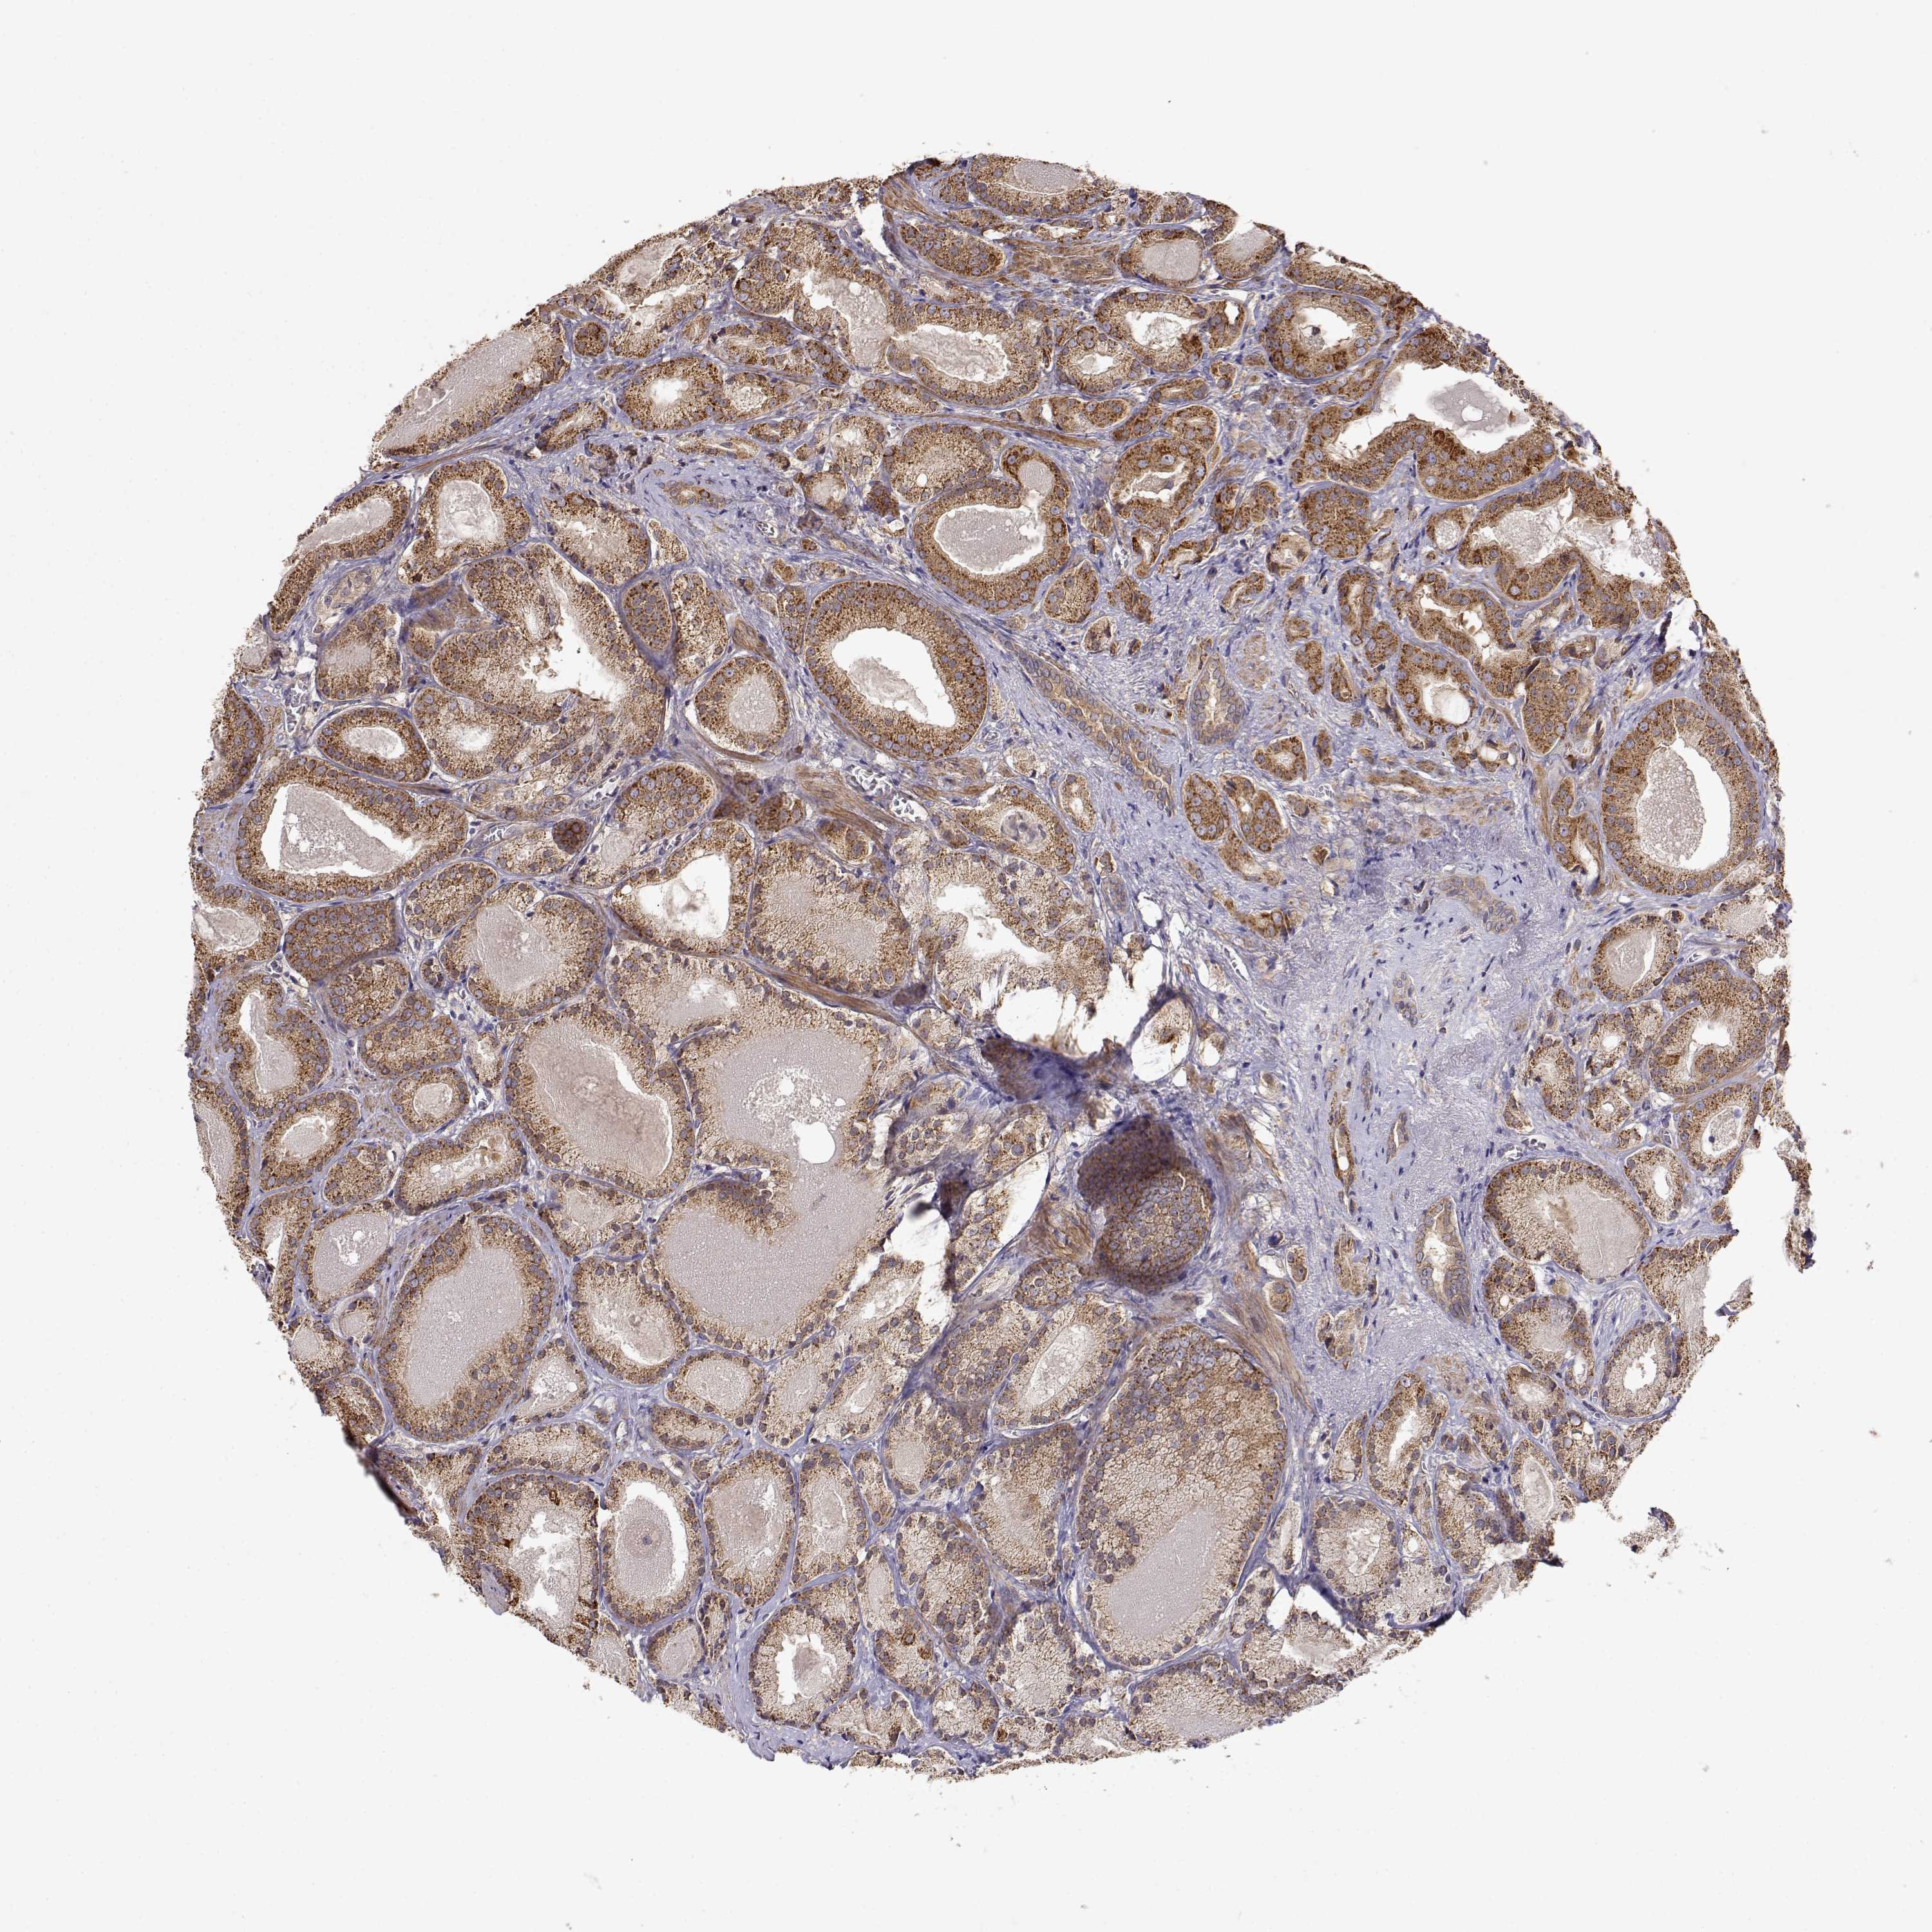

PROSTATE CANCER - Protein expressioni

A mouse-over function shows sample information and annotation data. Click on an image to view it in a full screen mode. Samples can be filtered based on level of antibody staining by selecting one or several of the following categories: high, medium, low and not detected. The assay and annotation is described here.

Note that samples used for immunohistochemistry by the Human Protein Atlas do not correspond to samples in the TCGA dataset.

Antibody stainingi

Antibody staining in the annotated cell types in the current human tissue is reported as not detected, low, medium, or high, based on conventional immunohistochemistry profiling in selected tissues. This score is based on the combination of the staining intensity and fraction of stained cells.

Each image is clickable and will lead to virtual microscopy that enables deeper exploration of all samples and also displays staining intensity scores, fraction scores and subcellular localization as well as patient and tissue information for each sample.

Antibody HPA073653

Staining

High

Medium

Low

Not detected

Intensity

Strong

Moderate

Weak

Negative

Quantity

>75%

75%-25%

<25%

None

Location

Nuclear

Cytoplasmic/membranous

Cytoplasmic/membranous,nuclear

Adenocarcinoma, High grade

Adenocarcinoma, NOS

Adenocarcinoma, Low grade